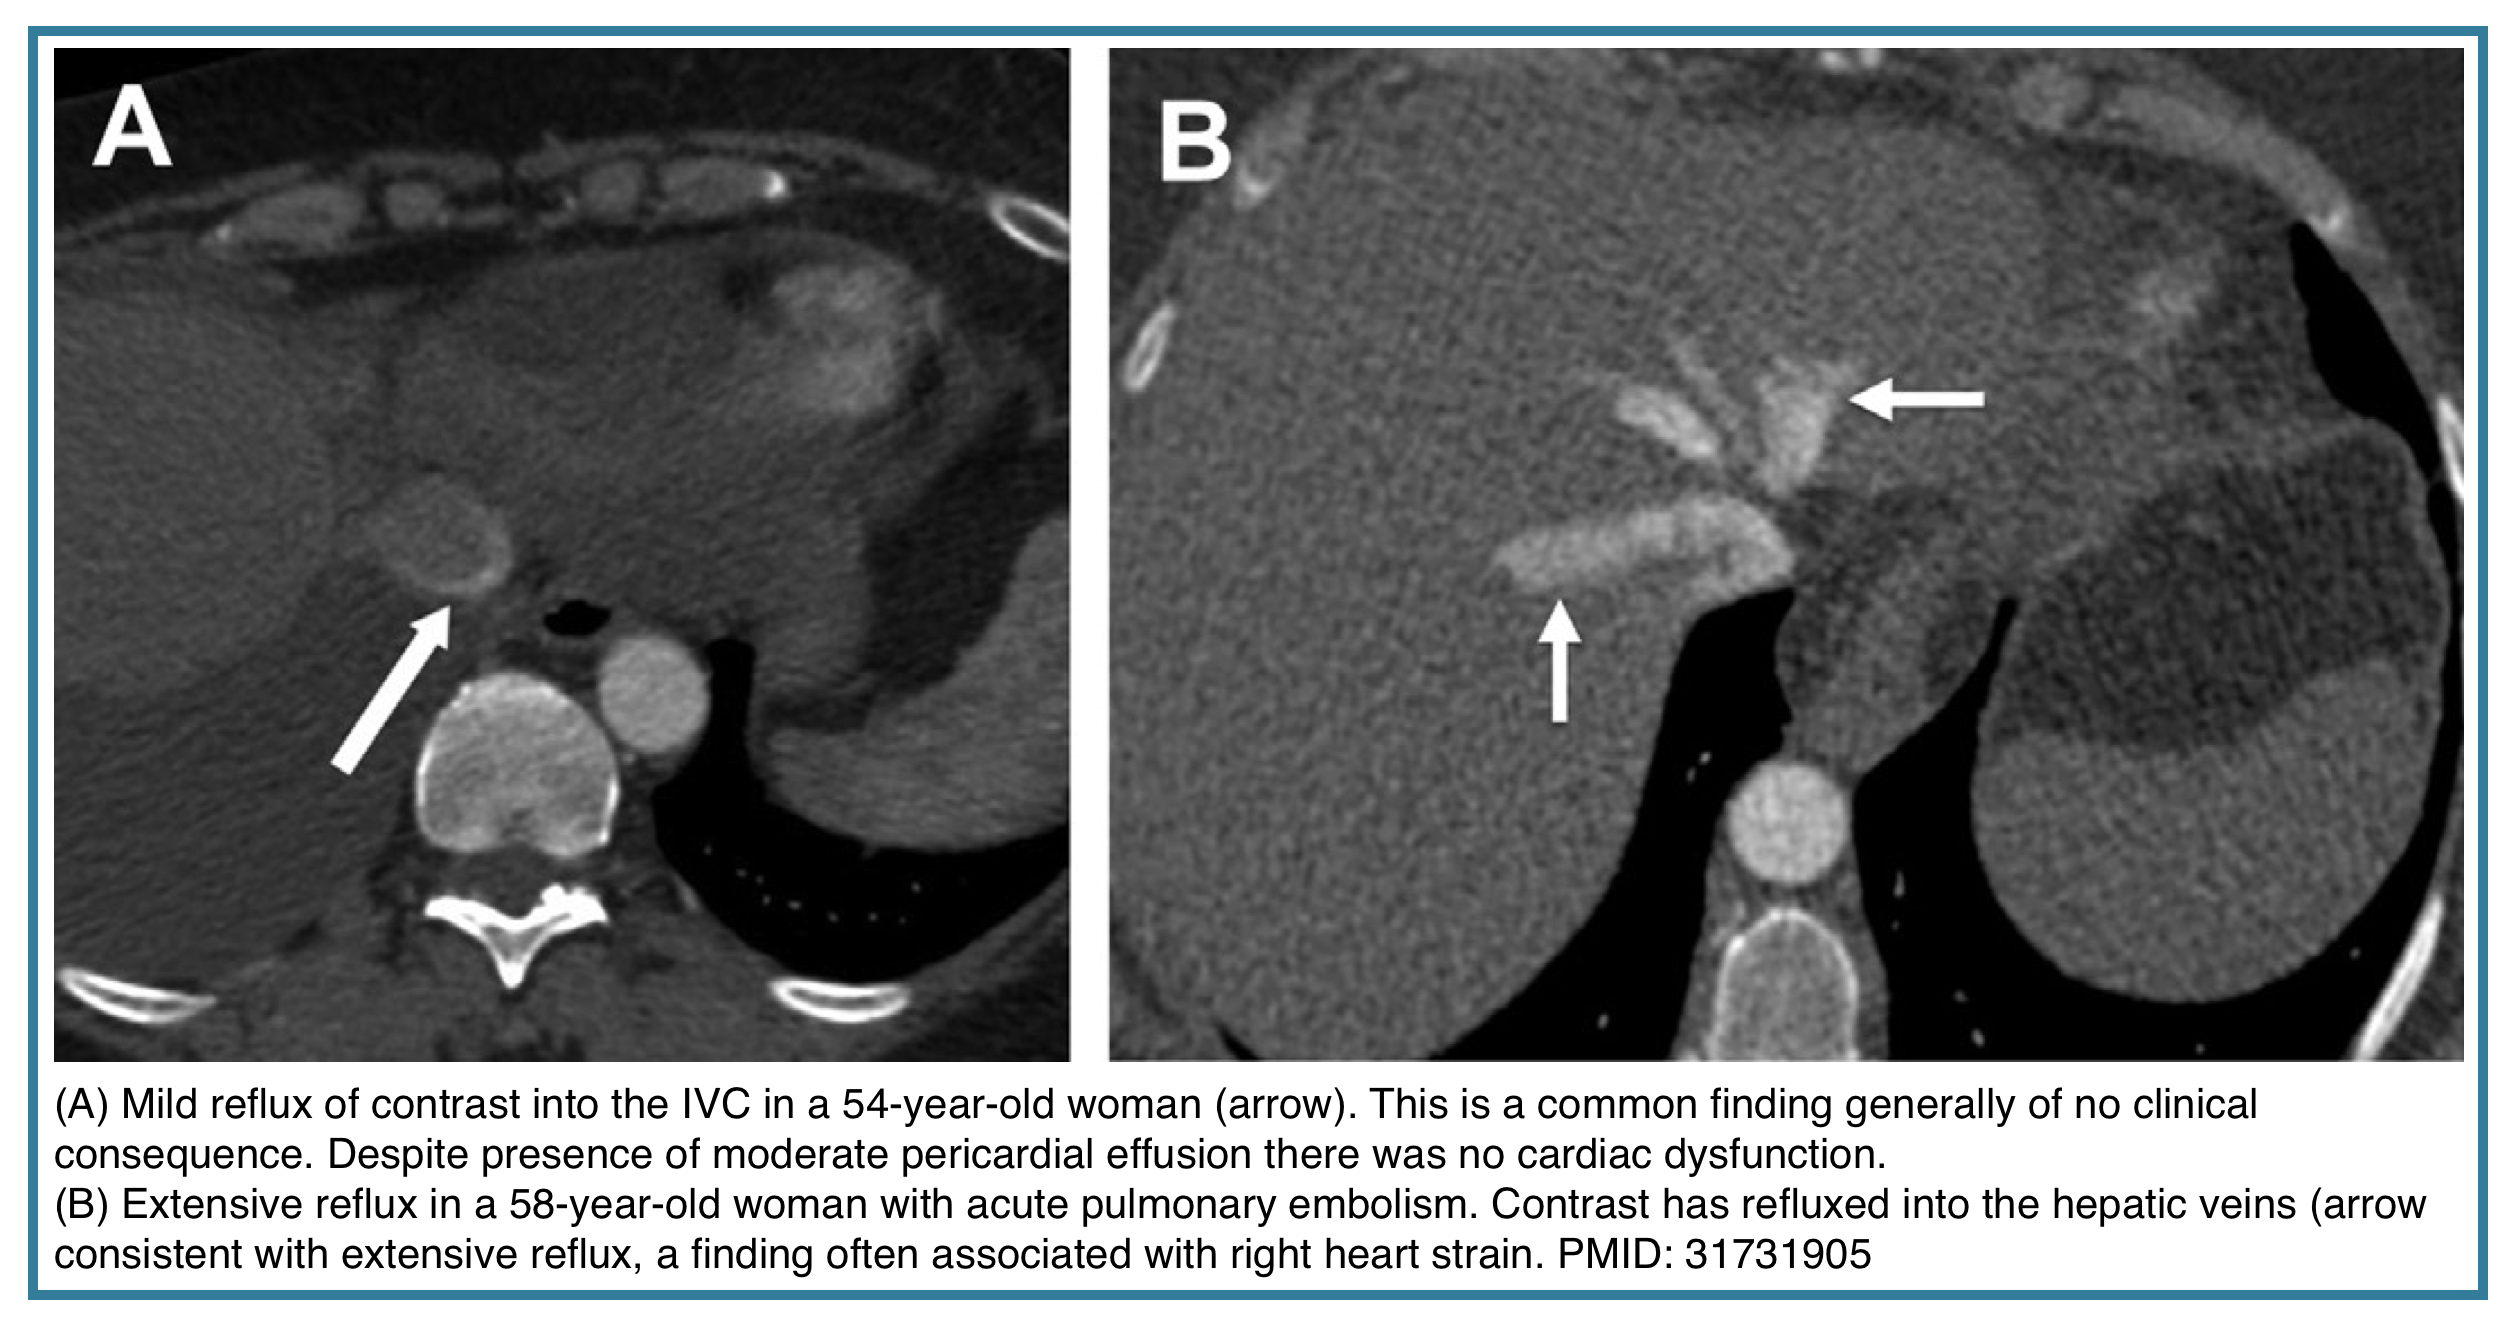

- Reflux of contrast into the inferior vena cava (IVC) and hepatic veins.